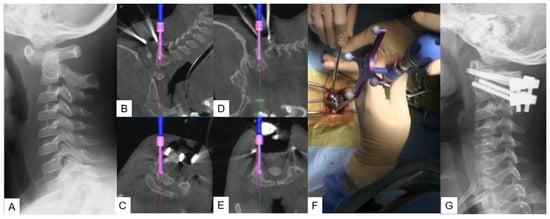

2.2.4. Minimally Invasive Cervical Pedicle Screw Fixation (MICEPS)

- Tanaka, M.; Fujiwara, Y.; Uotani, K.; Kadiri, V.; Yamauchi, T. C-Arm-Free Minimally Invasive Cervical Pedicle Screw Fixation (MICEPS): A Technical Note. Acta Med. Okayama 2020, 74, 551–556. [Google Scholar] [PubMed]